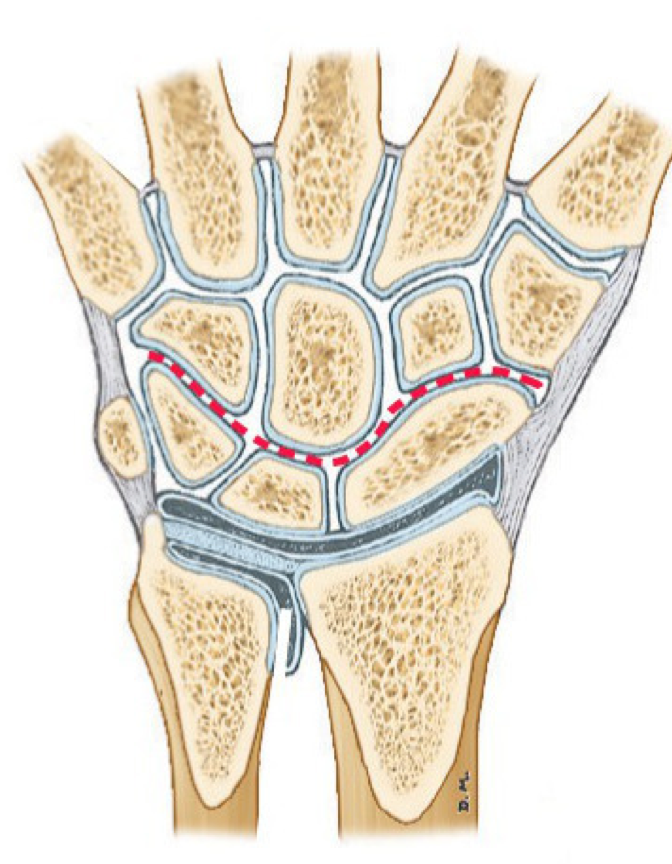

What joint is the wrist?

The radiocarpal joint

What forms the radiocarpal joint?

Articulation between the distal radius and 2 of the carpal bones: scaphoid and lunate N.B. the ulna is NOT involved

What type of joint is the wrist?

Synovial joint

What ligaments strengthen the wrist joint? Where do they strengthen it?

What is the ‘carpus’?

The wrist

How many bones make up the carpus?

8 small bones arranged in 2 rows

What joint is found between the carpals and the metacarpals?

The carpometacarpal joint (CMCJ)